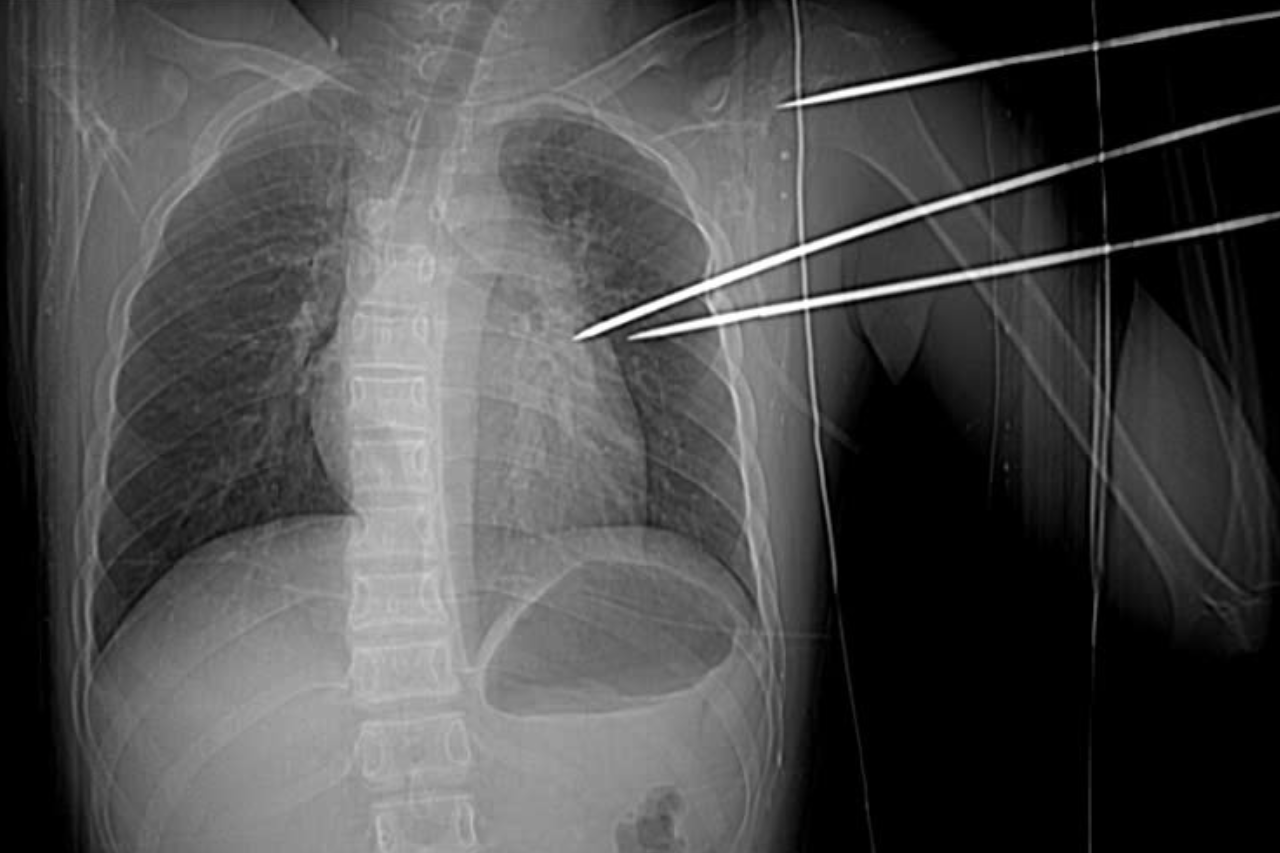

Hình ảnh chụp X-quang và cắt lớp vi tính cho thấy dị vật xuyên qua mặt sau vai trái và mô thùy trên phổi trái, đâm vào thành bên thất trái của tim, gây tràn máu màng tim.